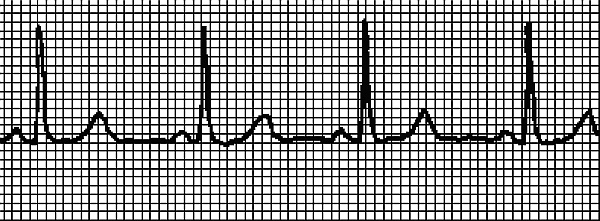

Что надо сделать до приезда врача и после снятия приступа Пароксизмальную тахикардию должен устранить врач. Если нам удастся справиться с приступом до приезда врача – замечательно! Но электрокардиограмма все же необходима, поскольку мы устраним только симптом, и ненадолго. Итак, действия при внезапной тахикардии таковы. • Прежде всего, надо успокоиться, не волноваться, поверить, что сердце надежно выдерживает кратковременную аритмию с ЧСС выше 200 единиц. И немедленно принять 40–50 капель корвалола, или корвалдина, или валокордина. • Несколько раз надавить на глазные яблоки четырьмя пальцами рук: надавливаем и отпускаем, надавливаем и отпускаем, и еще раз, и еще раз. • Медленно плавно и глубоко вдохнуть, затем на 30 секунд задержать дыхание, медленно и плавно выдохнуть. Как диагностируют тахикардию Если после снятия приступа больной решит поскорее забыть о случившемся – это неоправданная беспечность! Тахикардию надо диагностировать, то есть пройти осмотр у врача, сделать ЭКГ и суточный мониторинг по Холтеру (об этом исследовании читайте ниже, в разделе Возбудимость – еще одна функция сердца/Как уловить экстрасистолию ). Врач обязательно назначит клинический и биохимический анализы крови, анализ гормонов щитовидной железы, чтобы исключить или подтвердить «не сердечную» причину тахикардии. Возможно, понадобится пройти ультразвуковое исследование сердца. ЭКГ при тахикардии ... Для проведения электрокардиограммы не требуется никакой специальной подготовки. Но есть 2 рекомендации. 1. ЭКГ проводится после 15–20 минутного отдыха. Придя в поликлинику, не заходите сразу в диагностический кабинет, отдохните, чтобы на результатах кардиограммы не отразилась аритмия, связанная с ходьбой. 2. Перед исследованием не рекомендуется плотный прием пищи. Однако и натощак записывать ЭКГ не надо. На рис. 2 записан нормальный синусовый ритм, на рис. 3 ритм при синусовой тахикардии. ЭКГ записывали у одного и того же человека сначала в состоянии покоя, затем после нагрузки. Даже не имея медицинского образования, можно понять, что существенных изменений в работе сердца не произошло – только учащение сокращений. На рис. 4 записана несинусовая тахикардия. Водитель ритма смещен в предсердие. Если такая тахикардия легко устранится, то причина может быть не связана с болезнью сердца. Врач иногда снимает подобное состояние массажем! Это так называемый массаж каротидного синуса, который проводится в области сонной артерии (καρόω и означает «засыпать», по-гречески). Но без диагностики состояния, без ЭКГ «назначить» массаж нельзя, он не является безобидной процедурой и может нанести вред! Поэтому при пароксизмальной тахикардии ограничимся рекомендацией надавливать на глазные яблоки , которую мы уже приводили. При устойчивой предсердной аритмии можно заподозрить легочную недостаточность или инфаркт миокарда. ![]() Рис. 2. Синусовый ритм ![]()

Рис. 5. Желудочковая тахикардия Причины брадикардии, замедления сердечного ритма Частота сердечных сокращений может не только увеличиваться, но и замедляться. Сердцу тренированного человека, спортсмена, привыкшего к большим нагрузкам нет необходимости биться часто, потому что у него большая сократительная способность. Если одно сокращения равноценно полутора сокращениям «среднего» человека, ЧСС снижается до 50 ударов в минуту и ниже.... На знаменитой велогонке Тур де Франс пятеро велогонщиков одерживали победу по 5 раз. Один из спортсменов отличился тем, что брал кубок без перерыва пять лет подряд. Это испанец Мигель Индурайн, обладающий уникальными физиологическими особенностями. Средний объем легких взрослого мужчины составляет 6 л, а у Индурайна – 8 л. В норме по организму здорового человека прокачивается 3–4 л крови за 1 минуту, а сердце и легкие Индурайна при нагрузке способны повысить этот объем до 5–6 л. Так вот в состоянии покоя тренированное сердце этого спортсмена может ограничиться 28 ударами в минуту без ущерба для самочувствия! Такое замедление ритма называется физиологической брадикардией . И, конечно, она носит уже известный нам правильный синусовый характер. Синусовая брадикардия (рис. 6) обусловлена понижением автоматизма синусового узла, первичного водителя ритма, о котором мы говорили в начале этой главы. Если брадикардия не сопровождается дискомфортом в области сердца, затрудненным дыханием, головокружением и другими субъективными ощущениями, снижение ЧСС до 40 ударов в минуту можно считать вариантом нормы. Воздействие холода и голодание вызывают физиологическую брадикардию, которая быстро проходит в нормальных условиях. Брадикардия, которая сопровождается слабостью и головокружением (вследствие кислородного голодания головного мозга), требует выяснения ее причины. Возможные причины таковы. • Снижение функции щитовидной железы (гипотериоз). • Некоторые инфекционные заболевания, отравление свинцом или никотином. |